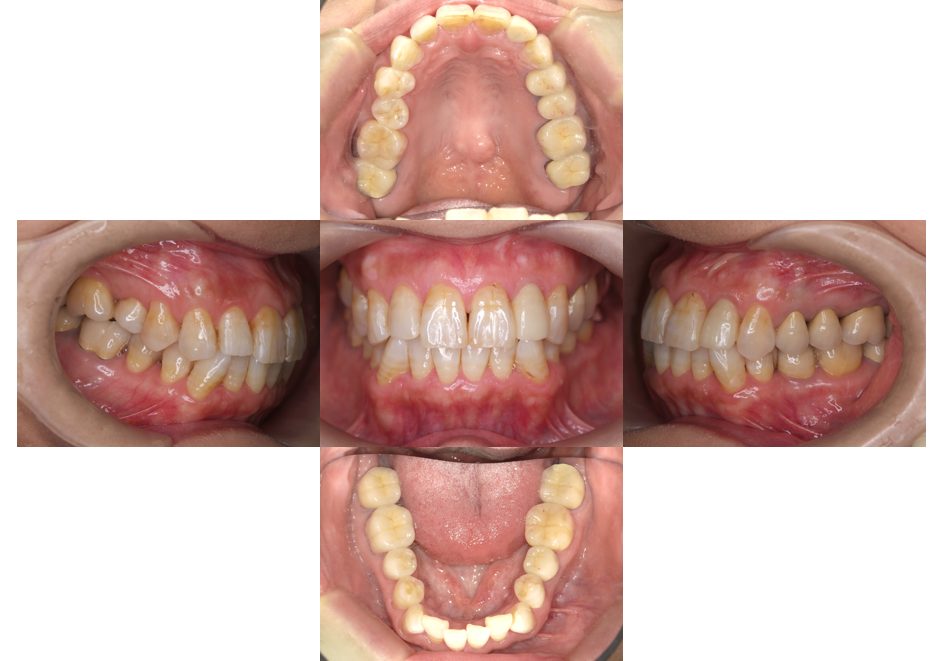

| 主訴 | 過去作成した右下の被せ物がずれて入っており、たまに腫れる。歯並びも気になる。 |

| 治療内容 | 矯正治療を行いました。 |

| 治療費 | 800,000円(税込み) |

| 治療期間 | 2年半(矯正治療期間 2年) |

| 治療回数 | 30回 |

| 想定されたリスク | 術前に基礎資料を整え分析し、セットアップモデル等でシミュレーションをしておかないと、予定通りの治療が行えないリスクがあった。 |